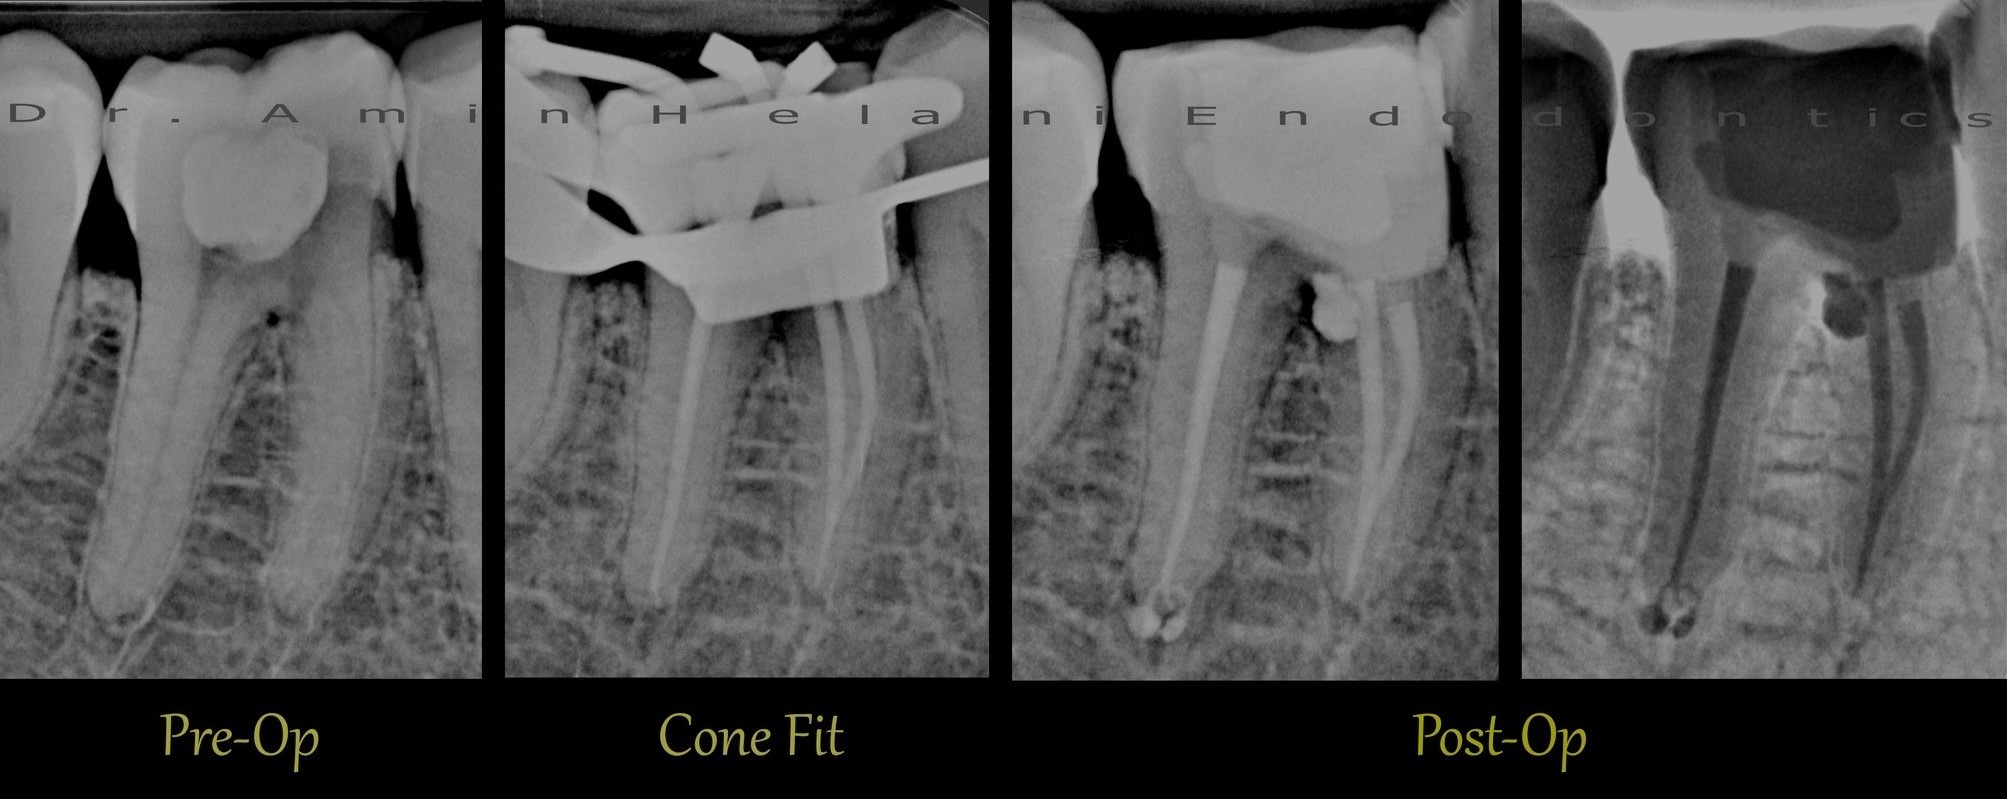

C-Shape Kanal